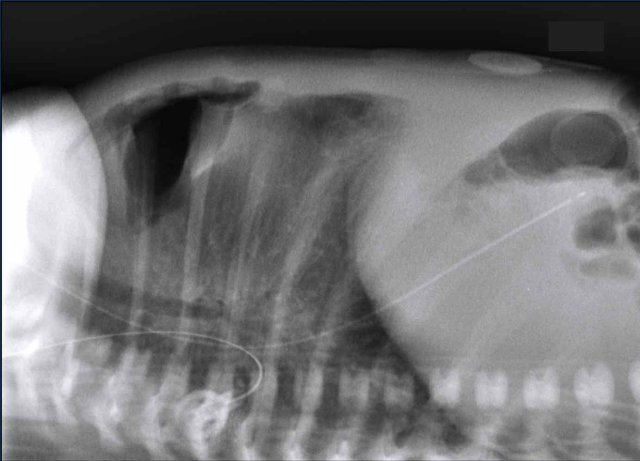

These images are of a full-term neonate with shortness of breath.

Images

Partial opacification of the left upper hemithorax.

Bowel structures are seen in the left hemithorax.

Shift of midline structures seen as deviation of the nasogastric tube (arrowhead).

The lateral chest film also demonstrates bowel loops in the chest.